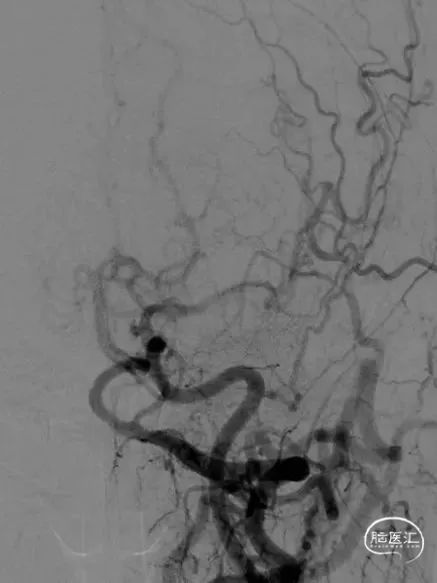

并行右侧颈动脉支架植入术,手术过程无特殊,植入Precise7-30mm支架。

右侧颈内动脉起始段狭窄

术后12个月复查影像提示支架形态良好

长期门诊随诊,无不适,二次手术1年后再次入院复查造影,双侧颈动脉支架情况良好。

术后15月复查显示左侧颈动脉支架形态良好,支架完全内皮化

左侧颈动脉支架术后即刻,3月,15月的DSA影像对比